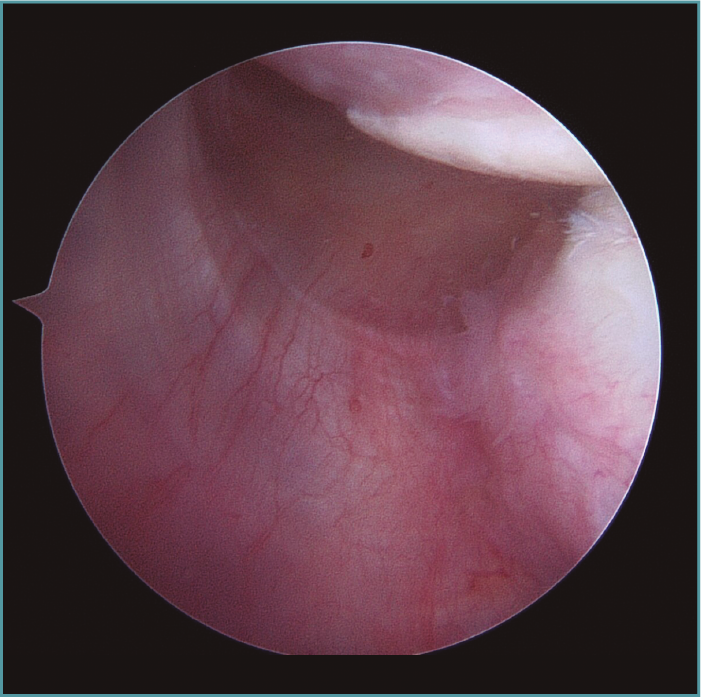

A excepción de los pacientes con significativos déficit óseos o recidivas con una mala calidad de tejido capsular, realizamos una técnica de reparación artroscópica. Operamos siempre con el paciente en decúbito lateral, con anestesia regional y general. Utilizamos siempre 4 portales instrumentales y un portal superior visual de exploración. Comenzamos nuestras cirugías con un portal de visión posterosuperior y un portal anterior de trabajo. Dependiendo de los hallazgos, realizamos las plicaturas capsulares que sean necesarias. En repetidas oportunidades encontramos hiatos intracapsulares, como por ejemplo entre el ligamento glenohumeral medio y superior, o laxitudes capsulares centrales, tratando los mismos con suturas de superior a inferior para generar una plicatura similar al capsular shift, incluso aumentando el espesor capsular (Figura 3). Luego de reparar estos defectos capsulares, seguimos nuestras plicaturas desde posterior, a través de un portal posteroinferior accesorio, colocando un anclaje con doble sutura, realizando la reparación y/o plicatura del haz posterior del ligamento glenohumeral inferior y achicando el receso inferior agresivamente siempre con anclajes de doble sutura (Figuras 4 y 5). Luego pasamos a un portal superior de visualización, dedicamos el tiempo necesario a liberar todo el labrum anteroinferior, despegando la cápsula anterior y el labrum del subescapular para movilizar e incluso acortar la cápsula, en ocasiones resecando parte de la misma para mejorar la plicatura; siempre utilizamos una sutura de tracción anterosuperior por fuera de la cánula para traccionar el tejido. Para poder llegar lo más cercano a hora 6, el primer anclaje anterior lo colocamos por un nuevo portal percutáneo transubescapular, utilizando arpones doble sutura, usando el primer par de suturas para llevar la cápsula y el labrum hacia la glena realizando sobre esta una sutura doble de tipo colchonero para mejorar la aposición capsular (Figura 6). Luego colocamos en la mayoría de los casos 2 anclajes más para terminar la reparación, en general 4 arpones. De haber un intervalo de rotadores amplio, no vacilamos en cerrarlo con suturas (Vídeo anexo).

Figura 3. Visión desde portal posterior del hombro derecho. Paciente con inestabilidad glenohumeral y gran laxitud anterior. Se visualizan 3 plicaturas lado a lado generando un acortamiento y engrosamiento de la cápsula.